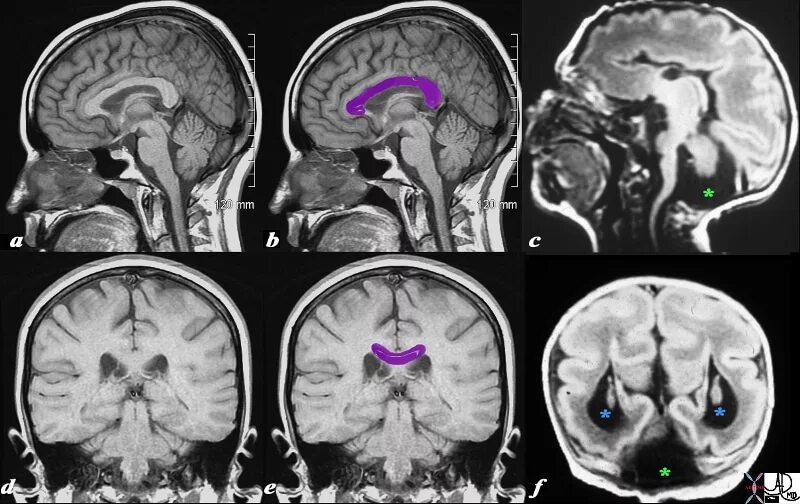

Денди уокер у взрослых